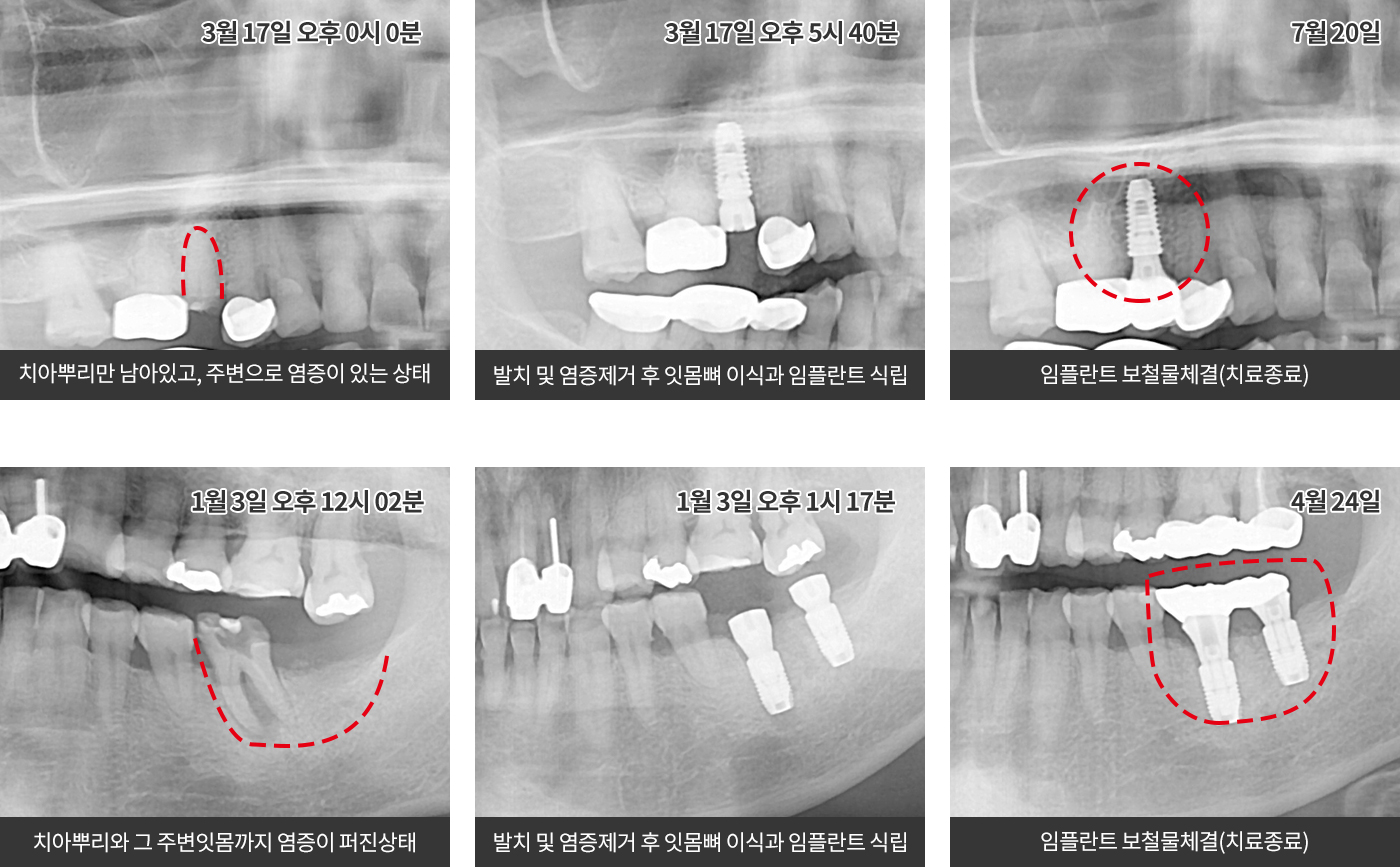

즉시식립 임플란트

발치와 동시에 임플란트를 식립하여 치료기간 및 횟수를

줄이는 동시에 빠르고 정확하게 수술합니다.